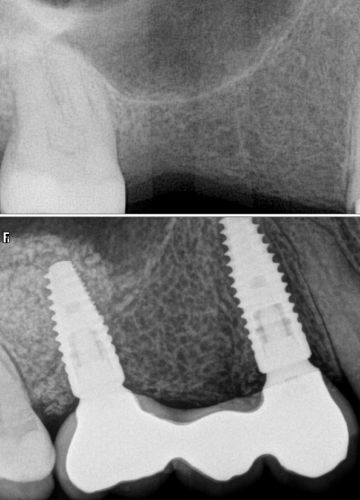

Metālkeramikas tilts + 2 zoba implanti

''Sinus lift'' un divu zobu implantu ievietošanas operācija, smaganu formētāju ievietošana

Pēc 4 mēnešiem tika izgatavots metālkeramikas tilts